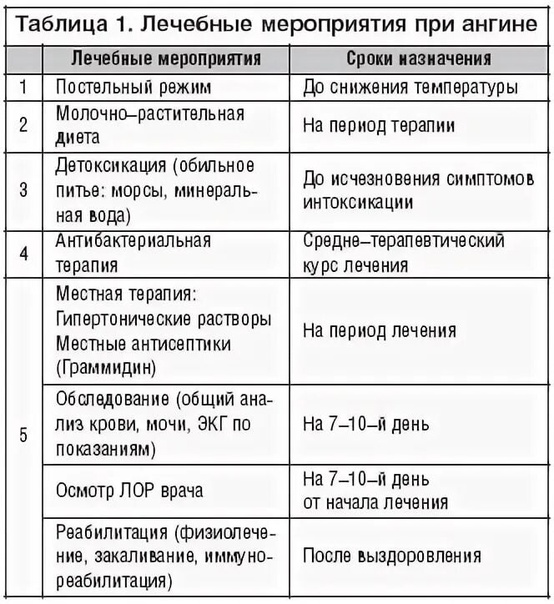

Процесс лечения лакунарной ангине

В первую очередь, пациенту назначается постельный и питьевой режим. Лакунарная ангина у взрослых лечится при помощи сульфаниламидных препаратов и ацетилсалициловой кислоты. Средства, понижающие температуру, необходимо принимать при температуре выше тридцати восьми градусов.

Также лечебный процесс включает.

- Прием антибиотиков. Зачастую лечение заболевания проводится в домашних условиях. Обязательным условием терапии являются антибиотики при лакунарной ангине. Они позволяют быстрее восстановиться пациенту и вовремя устранить возбудителя. Длительность лечебного курса составляет от пяти до десяти дней в зависимости от тяжести болезни. Также прием антибиотиков позволяет снизить вероятность возникновения осложнений. Взрослым назначают такие средства, как Сумамед, Азитромицин, Флемоксин Солютаб.

- Применение противовирусных средств. Назначаются в том случае, ангина была вызвана вирусами. Тогда лечение включает прием средств в виде Циклоферона, Амиксина, Кагоцела.

- Местное лечение болезни. Данный метод является обязательным условием терапии. Полоскания и орошения горла направлены на дезинфекцию полости и уменьшению симптоматики. К самым эффективным местным средствам относят: полоскания горла раствором Фурацилина, содовым и солевым раствором с йодом.; полоскания настоями лекарственных трав в виде ромашки, календулы, шалфея; орошение горла раствором морской соли; орошение горла лекарственными средствами в виде Мирамистина, Гексорала, Каметона; рассасывание противовоспалительных и антибактериальных таблеток в виде Граммидина, Стрепсилса, Лизобакта, Фарингосепта.

Если проявилась лакунарная ангина у детей, то лечение включает прием антигистаминных средств в виде Зодака, фенистила, Эриуса. Такие препараты способствуют снятию отечности миндалин и глотки. При высокой температуре детям рекомендуют ставить свечи Цефекон или давать Парацетамол и Ибупрофен в сиропе.

Также в детском возрасте обязательно назначают антибиотики в виде Амоксиклава, аугментина или Флемоксина. Наряду с этим нужно принимать средства, которые нормализуют микрофлору кишечника.

Так как дети до определенного возраста не имеют полоскать горло, то вместо этого стоит проводить орошение горла настоями лекарственных трав и раствором Фурацилина. Также можно использовать Мирамистин. Для повышения иммунных сил детям назначают свечи Виферон или таблетки Анаферон.

Не стоит забывать о том, что в основные правила лечения входит следующее.

- Соблюдение постельного режима. От прогулок на несколько дней нужно отказаться.

- Соблюдение питьевого режима. Если ребенок отказывается пить воду, то можно давать компоты, морсы и чаи. Особенно, это касается грудничков. Это позволит избежать обезвоживания организма.

- Сбалансированное и правильное питание. В период болезни пациента не стоит заставлять кушать. Но если больной не отказывается, то лучше давать супчики или различные овощные и фруктовые пюре.

Проводить ингаляции и любые прогревающие процедуры категорически запрещено.

Чем лечить ангину у детей

Нужно чётко следовать всем рекомендация лечащего педиатра для скорейшего выздоровления малыша. Эффективное лечение ангины подразумевает обильный приём жидкости, жаропонижающих, антибиотиков, эубиотиков, антигистаминных средств, полоскания горла и витаминотерапии.

Нужно чётко следовать всем рекомендация лечащего педиатра для скорейшего выздоровления малыша. Эффективное лечение ангины подразумевает обильный приём жидкости, жаропонижающих, антибиотиков, эубиотиков, антигистаминных средств, полоскания горла и витаминотерапии.

Важно! Гнойная ангина не допускает любые разогревающие процедуры, такие как компрессы, разогревающие мази и крема в шейной области. Один из способов лечения ангины — это полоскание горла для детей старшего возраста и обработка аэрозолями и спреями маленьких детей

Но полоскание горла это только 1 из вспомогательных способов, т. к. основное лечение заключается в приёме антибактериальных средств

Один из способов лечения ангины — это полоскание горла для детей старшего возраста и обработка аэрозолями и спреями маленьких детей. Но полоскание горла это только 1 из вспомогательных способов, т. к. основное лечение заключается в приёме антибактериальных средств.